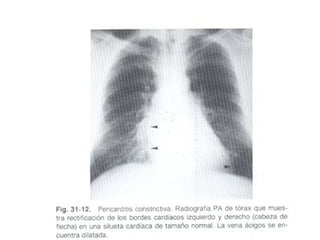

PERICARDITIS CONSTRICTIVA

Las  calcificaciones pericárdicas resultan de la organización de exudado o sangre en saco pericárdico, que puede estar asociada o no con pericarditis constrictiva. La pericarditis constrictiva es más frecuente en tuberculosis. Sin embargo, pueden verse placas calcificadas pericárdicas en el 5 % de los pacientes con enfermedad reumática crónica. La calcificación es más densa en la zona de los surcos interventriculares y auriculoventriculares.

Las calcificacionespericárdicas resultan de la organización de exudado o sangre en saco pericárdico, que puede estar asociada o no con pericarditis constrictiva. La pericarditis constrictiva es más frecuente en tuberculosis. Sin embargo, pueden verse placas calcificadas pericárdicas en el 5 % de los pacientes con enfermedad reumática crónica. La calcificación es más densa en la zona de los surcos interventriculares y auriculoventriculares.